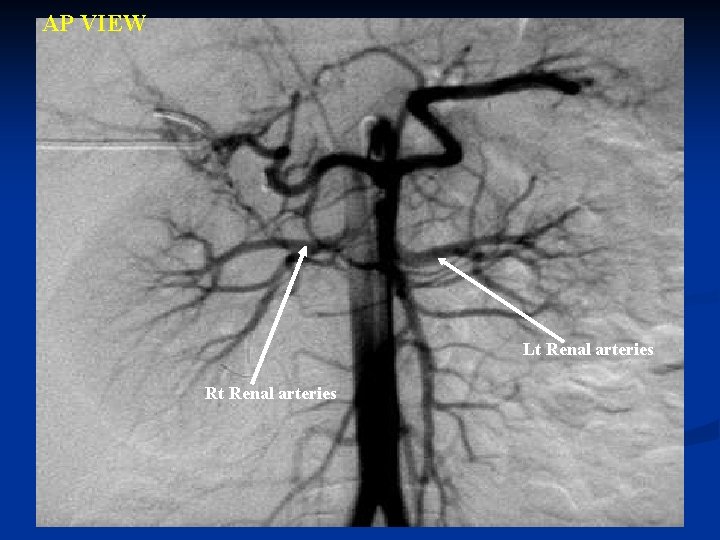

Renal arteries 1. Two large arteries 2. Arises from side of aorta, immediately below SMA 3. Nearly a right angle with the aorta 4. Right is longer than left 5. Before reaching hilus of the kidney, each artery divides into four or five branches 6. Left is somewhat higher than the right

AP VIEW Lt Renal arteries Rt Renal arteries